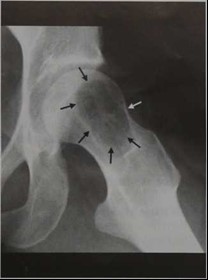

Ювенильная костная киста головки бедренной кости. Рентгенологическое исследование шейки левой бедренной кости в прямой проекции у женщины 27 лет с ювенильной кистой. Типичное доброкачественное, четко ограниченное, географическое поражение.

Больной гиперстенического телосложения, высокого роста, среднего питания. Патологии со стороны внутренних органах не обнаружено. Анализы крови и мочи - без отклонений от нормы. Кожа над образованием была не измененной, пальпация безболезненной, отечность отсутствовала. Конфигурация правого голеностопного сустава сохранена (рис. 1). Активные движения в суставах фаланг пальцев правой стопы были в пределах нормальных амплитуд. Определялось ограничение тыльной флексии правой стопы до 15°.

Рис. 1. Больной Ч., 28 лет. Внешний вид правого голеностопного сустава

Рис. 2. Больной Ч., 28 лет. Аневризмальная костная киста правой таранной кости во фронтальных и сагиттальных проекциях: а - рентгенограммы; б - компьютерные томограммы